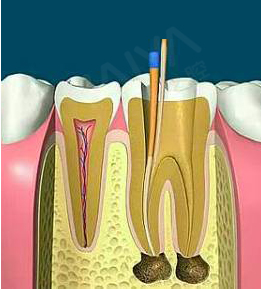

麦芽显微根管治疗

通过机械和化学方法去除根管内的大部分感染物,并通过充填根管、封闭冠部,防止发生根尖周病变或促进已经发生的根尖周病变的愈合。

适应症:牙根尖周炎